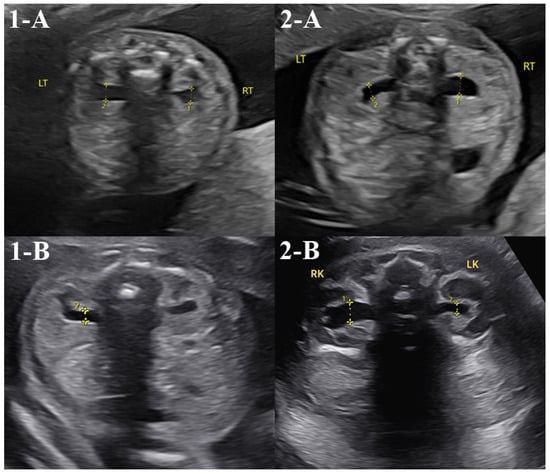

Detailed prenatal ultrasounds were performed in 43 cases (74.1%, 43/58) by the first trimester and in 35 cases (60.3%, 35/58) by the second trimester. No abnormalities were detected in the first-trimester nuchal translucency scan, while two cases showed abnormalities in the second-trimester detailed ultrasound. The two cases involved transfers of single, low-level, whole-type mosaic embryos of chromosomes 9 and 1, respectively (Table 3). Both showed mild renal pelvis dilatation in the second trimester, but one case resolved to normal findings in the third trimester, and the other was confirmed to be normal after birth (Figure 1). Both cases that showed abnormal findings on the prenatal ultrasound underwent amniocentesis, and both cases had normal karyotype and chromosomal microarray analysis results.

Figure 1.

Abnormal prenatal detailed ultrasound cases. Asterisk means anteroposterior renal pelvic diameter. In the second-trimester detailed ultrasound, two cases exhibited abnormal findings. Case 1 showed mild bilateral renal pelvis dilation on the detailed ultrasound performed at 22 weeks (1-A, anteroposterior renal pelvic diameter left 4.0mm, right 4.5 mm). However, follow-up examinations at 24 weeks confirmed normal findings bilaterally (1-B). Case 2 demonstrated mild right renal pelvis dilation on the detailed ultrasound performed at 21 weeks (2-A, anteroposterior renal pelvic diameter right 4.3 mm), and the same findings were noted on another detailed ultrasound at 36 weeks (2-B, anteroposterior renal pelvic diameter right 8.0 mm). However, postnatal examination confirmed normal findings bilaterally in the newborn.